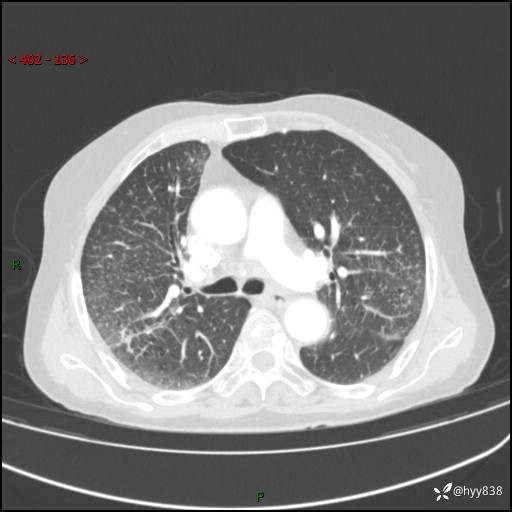

胸部CT增强(外院平扫)